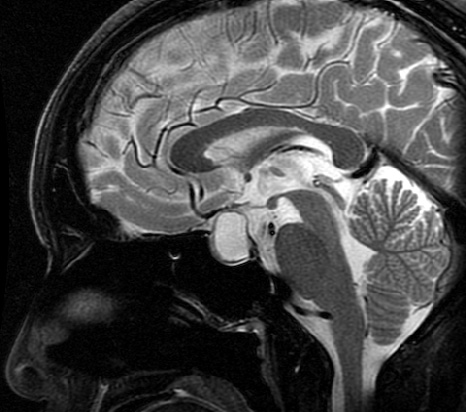

【ラトケ嚢胞】

非腫瘍性病変であり、下垂体の中にもともと存在する袋が拡大したものです。

30~60歳代に多い病気です。

無症状であれば基本的には経過観察を行いますが、大きくなり色々な症状が出現しているときには嚢胞の開放術を推奨致します。

ほとんどは経蝶形骨洞手術で改善します。